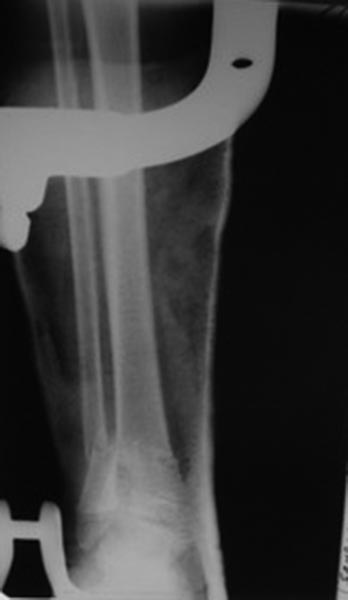

Переломы оскольчатые обеих бёдер в н/3, открытые. Раны ушиты в отличном состоянии.

На одном бедре межмыщелковый перелом и там мыщелки немного разъехались. Голень там тоже сломана в н/3 обе кости. Снимок голени в боковой проекции сделан не был.

Глубокоуважаемый Игорь. Есть ли в вашем отделении ЭОП? Переломы бёдер не простые. Я бы не стал рассчитывать на скелетное вытяжение. Не очень понятно где какое бедро. Левые снимки – по моему мнению бедро надо оперировать с артротомией: необходимо убрать осколки по передней поверхности перелома – они гарантировано будут мешать движениям. Малоинвазивное удаление может быть неудачным. Синтез мыщелков имеющимися у Вас спицами под контролем глаза и пальца. Кстати, в суставе могут быть обнаружены различные неожиданности. Общую фиксацию можно осуществить в АНФ Илизарова с встречной компрессией мыщелков. Правые снимки. Тоже высокоэнергетический перелом и критическое смещение отломков. Так оставлять, ИМХО, не стоит. Велика вероятность массивной интерпозиции между отломками. Отломки ротированы и это может вызвать нарушение сращения,ремоделирования кости. В качестве варианта: наложение АНФ Илизарова, разрез, «ручная» репозиция отломков «по месту». Дистальные перекрещивающиеся спицы я бы провёл через мыщелки бедра. АНФ будут оптимальны в спице-стержневом исполнении. С уважением!